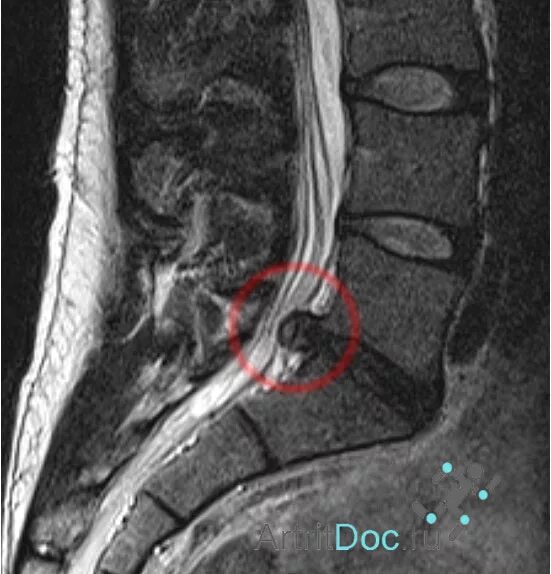

Как выглядит грыжа позвоночника на мрт